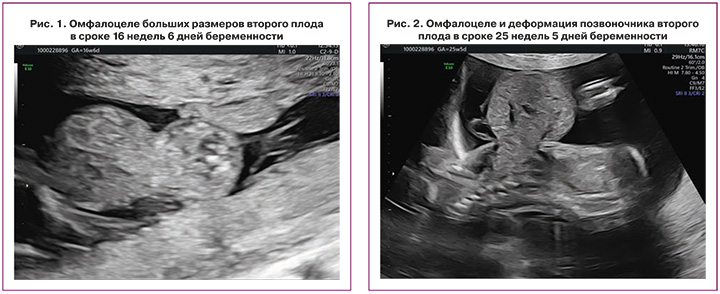

При исследовании в сроке 16 недель 6 дней в Центре подтвержден предполагаемый тип многоплодия: монохориальная диамниотическая двойня и отсутствие ультразвуковых признаков патологии у первого плода; у второго плода диагностированы омфалоцеле больших размеров, содержащее петли кишечника и печень, деформация позвоночника (рис. 1, 2).

На повторном перинатальном консилиуме диагностировано омфалоцеле второго плода в сочетании с деформацией позвоночника (рис. 2). Специалистами медицины плода, акушерами-гинекологами и неонатальными хирургами пациентка была предупреждена о неблагоприятном прогнозе для жизни у второго плода в связи с наличием омфалоцеле больших размеров [37], проинформирована о возможности проведения селективного фетоцида [4, 21], а также риске прерывания беременности, преждевременных родов, низкой массы тела анатомически нормального близнеца при рождении и его перинатальной смертности как при выжидательной тактике [22], так и при внутриутробном вмешательстве [4, 21].